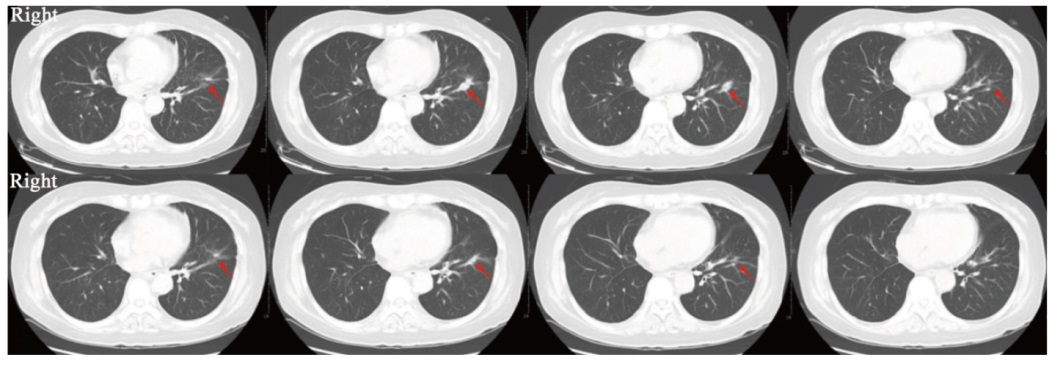

背景与目的:鞘内化疗是治疗实体瘤脑膜转移(leptomeningeal metastases,LM)的主要方法之一。既往的Ⅰ期临床研究证实了鞘内程序性死亡蛋白-1(programmed death-1,PD-1)抑制剂治疗黑色素瘤LM的安全性和潜在疗效。系统化疗联合PD-1抑制剂的协同抗肿瘤作用已被广泛认可。本研究旨在探索鞘内注射培美曲塞联合PD-1抑制剂治疗实体瘤LM的安全性及可行性。 方法:以广州医科大学附属惠州医院/惠州市第三人民医院收治的实体瘤LM患者为研究对象,采用“3+3”剂量递减策略,寻找推荐的安全给药剂量。培美曲塞给药方案为初始诱导治疗2次/周,连续2周;随后巩固治疗1次/周,连续4周;治疗有效的患者给予每个月1次维持治疗。PD-1抑制剂给药从第4次培美曲塞给药开始,每2周1次,连续6周;随后对治疗有效的患者,与培美曲塞同时给予每个月1次维持治疗。单次给药起始剂量为PD-1抑制剂(特瑞普利单抗)40 mg、培美曲塞15 mg。主要研究终点为安全性及推荐给药剂量,安全性基于不良反应进行评估。同时观察临床有效率(clinical response rate,CRR)、疾病控制率(disease control rate,DCR)和总生存期(overall survival,OS)。本研究经广州医科大学附属惠州医院/惠州市第三人民医院伦理委员会审批通过(伦理编号:2024-KY-029-01)。 结果:2024年6—9月共入组7例患者(男性3例,女性4例,中位年龄57岁),包括非小细胞肺癌6例和乳腺癌1例。所有患者的脑脊液(cerebrospinal fluid,CSF)细胞学检查结果均为阳性。6例存在LM相关神经功能障碍。5例存在LM相关影像学异常。6例完成诱导及巩固治疗并接受维持治疗。1例因细菌性脑膜炎未完成巩固期最后1次PD-1抑制剂鞘内给药,感染控制后接受维持治疗。总不良反应发生率为100%(7/7),包括骨髓抑制7例(100.00%)、转氨酶升高3例(42.86%)、乏力2例(28.57%)和甲状腺功能减退1例(14.29%)。其中3级不良反应发生率为42.86%(3/7),全部为骨髓抑制。免疫相关不良反应(immune-related adverse event,irAE)发生率为14.29%(1/7),为Ⅱ级甲状腺功能减退。未见剂量限制毒性(dose-limiting toxicity,DLT)发生,推荐剂量为PD-1抑制剂40 mg联合培美曲塞15 mg。3例患者神经功能改善,1例CSF细胞学检查结果转阴,2例影像学缓解。根据神经肿瘤疗效评估(response assessment in neuro-oncology,RANO)标准,CRR为57.14%(4/7),DCR为100%(7/7)。3例出现远隔效应,分别表现为脑转移灶、原发肺病灶及纵隔淋巴结缩退。截至2025年4月10日,1例死亡,中位随访时间为7.7(5.9~9.3)个月。中位OS未达到。6个月OS率为85.71%。 结论:鞘内注射培美曲塞联合PD-1抑制剂治疗非小细胞肺癌等实体瘤LM患者显示出良好的安全性和可行性,并且具有潜在的临床疗效。

Background and purpose: Intrathecal chemotherapy is one of the mainstay treatment options for leptomeningeal metastases (LM) from solid tumors. A previous phase Ⅰ study demonstrated the safety and potential efficacy of intrathecal anti-programmed death receptor 1 (anti-PD-1) for LM from melanoma. The synergistic efficacy of systemic chemotherapy combined with anti-PD-1 has been widely known. This study aimed to evaluate the safety and feasibility of intrathecal chemotherapy (pemetrexed) and anti-PD-1 (toripalimab) for LM patients from solid tumors. Methods: The subjects were patients with LM from solid tumors who were treated at Affiliated Huizhou Hospital of Guangzhou Medical University/Third People’s Hospital of Huizhou City. A 3+3 dose de-escalation strategy was implemented to determine the recommended dose with an initial dose of PD-1 inhibitor (toripalimab) 40 mg and pemetrexed 15 mg. Pemetrexed was administered twice weekly for the initial 2 weeks of induction therapy, once weekly for the subsequent 4 weeks of consolidation therapy, and once monthly during maintenance therapy. PD-1 inhibitor was initiated at the 4th administration of pemetrexed, administered every 2 weeks for 6 weeks; subsequently, responders continued monthly maintenance therapy alongside pemetrexed. The primary objective was to assess safety based on adverse events and the recommended dose. All participants were observed to investigate the clinical response rate (CRR), disease control rate (DCR) and overall survival (OS). This study was approved by the ethics committee of Affiliated Huizhou Hospital of Guangzhou Medical University/Third People’s Hospital of Huizhou City (ethics number: 2024-KY-029-01). Results: Seven patients (male: 3, female: 4, median age: 57 years) were enrolled between June and September 2024, including non-small cell lung cancer (6) and breast cancer (1). All patients presented with positive cerebrospinal fluid (CSF) cytology. Six patients presented LM-related neurological dysfunction. Five patients showed LM-related neuroimaging findings. Six patients completed the induction and consolidation therapy, and subsequently received maintenance therapy. One patient, due to bacterial meningitis, did not complete the final administration of toripalimab during consolidation therapy, and maintenance therapy was administered after infection control. Adverse events rate was 100% (7/7), including myelosuppression (100.00%, n=7), elevation of hepatic aminotransferases (42.86%, n=3), fatigue (28.57%, n=2) and hypothyroidism (14.29%, n=1). Three (42.86%) patients had grade 3 adverse events (myelosuppression). The immune-related adverse event (irAE) rate was 14.29%, manifested as hypothyroidism (Grade 2). No dose-limiting toxicity (DLT) was observed. Thus, no de-escalation was applied. The recommended dose was determined to be PD-1 inhibitor 40 mg in combination with pemetrexed 15 mg. Three patients showed improved neurological dysfunction, 1 with CSF cytological response, and 2 with neuroimaging improvement. CRR was 57.14% (4/7) by response assessment in neuro-oncology (RANO) proposal criteria. DCR was 100% (7/7). Three patients exhibited abscopal effects with regression of brain metastasis lesions, primary lung lesion and mediastinal lymph nodes, respectively. As of April 10, 2025, 1 patient died. The median follow-up time was 7.7 (5.9-9.3) months. The median OS was not reached with a 6-month OS rate of 85.71%. Conclusion: The combination therapy of intrathecal pemetrexed and a PD-1 inhibitor was well-tolerated and feasible, while also exhibiting potential clinical efficacy in treating LM from solid tumors including non-small cell lung cancer.